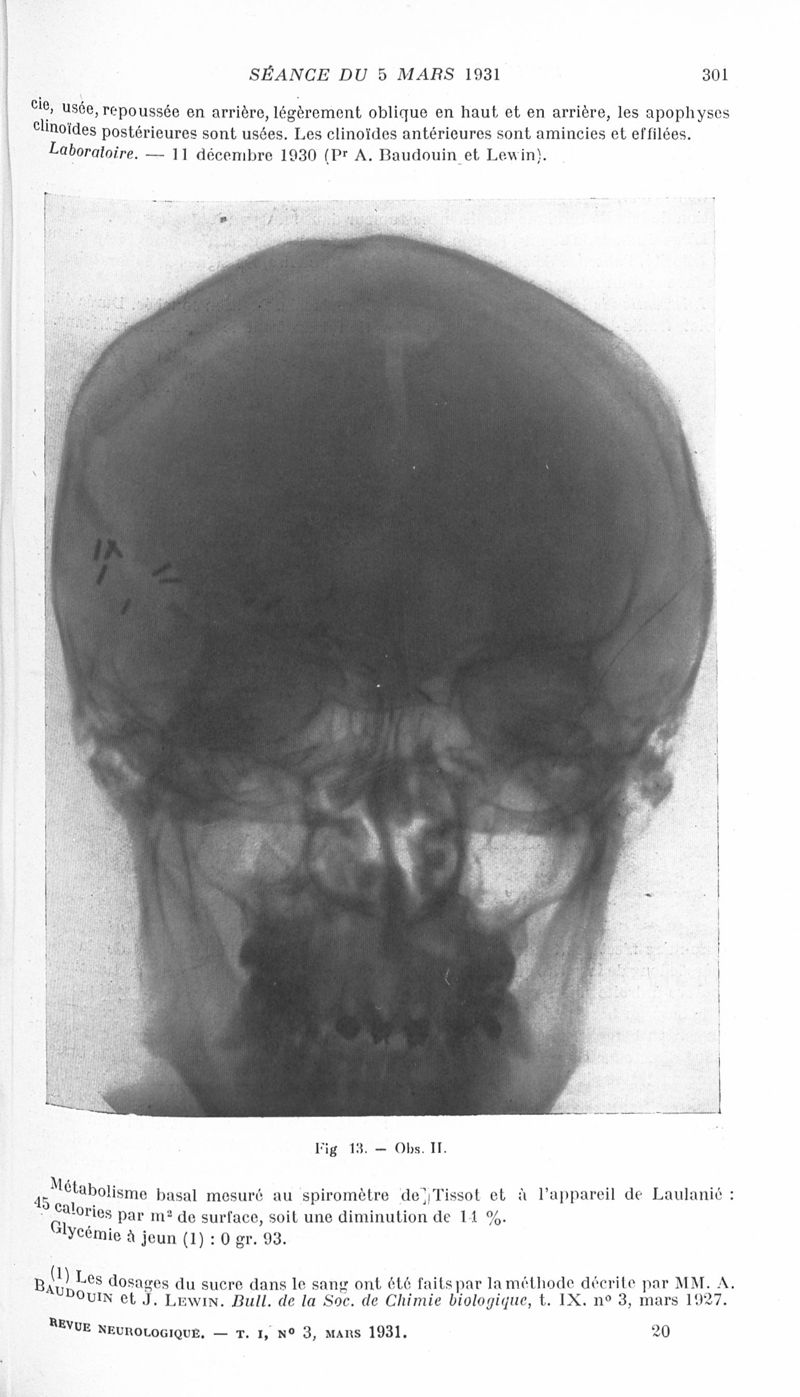

Revue neurologique

1931, vol 1. - Paris : Masson , 1931.